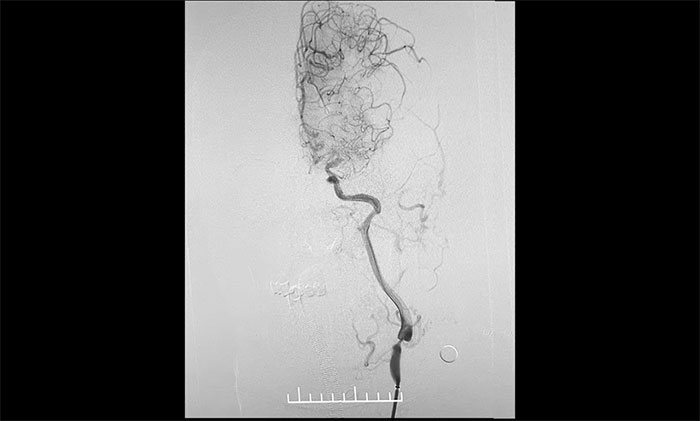

術中,席剛明教授、王貴平博士克服血管迂曲困難,經(jīng)過多次嘗試,多次球囊擴張、“按摩”后,最終順利釋放密網(wǎng)支架至左頸內動脈眼動脈段、左頸內動脈床突段、左頸內動脈海綿竇段。造影及3D造影見,動脈瘤瘤內造影劑明顯滯留,左頸內動脈、左大腦前動脈顯影可,載瘤動脈通暢,獲得了理想的血管重建。復查造影,左頸總動脈造影見左頸總動脈、左頸內動脈、左大腦前動脈顯影可。CT見支架打開貼壁滿意,XperCT未見顱內出血,手術圓滿完成,順利拆除“不定時炸彈”并打通大腦生命線。

▲ 頸動脈重度狹窄解除,打通大腦生命線

▲ 順利拆除“不定時炸彈”